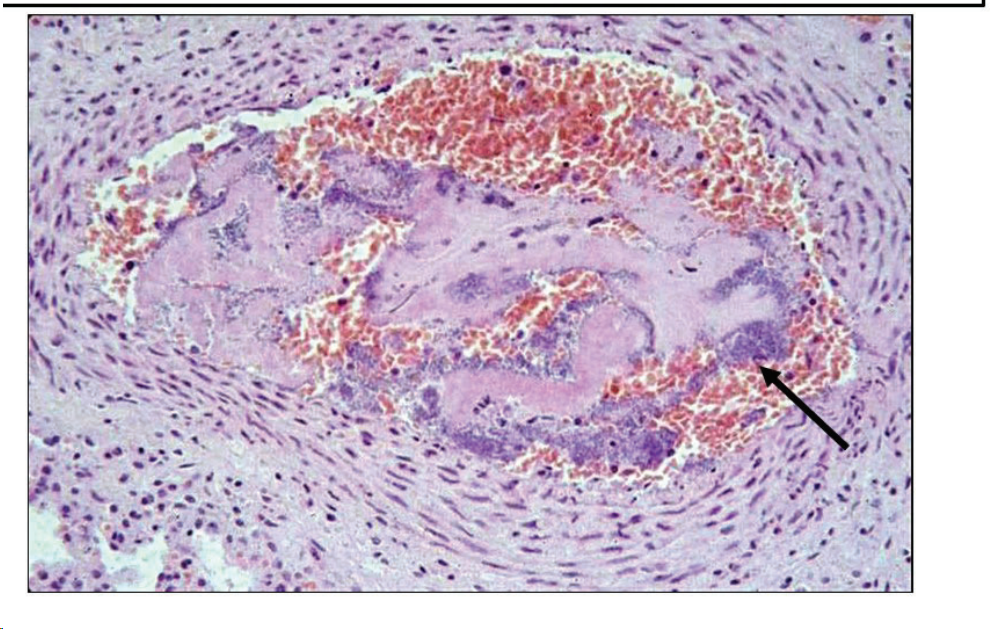

Infarto rojo o hemorrágico

Etiopatogenia:

- Oclusión arterial brusca en órganos con doble circulación o colaterales (hígado, pulmón, bazo).

- 1ª: necrosis por anoxia.

- 2ª: encharcamiento de sangre.

- Impedimento brusco al retorno venoso (órganos con hiperemia pasiva): torsión de útero, intestino, vólvulo intestinal.

Aspecto macroscópico:

- Zona prominente, de color rojo-negruzco.

- Límites netos (“cartográficos”).

- Consistencia ligeramente menor.

Microscopía:

- Igual al infarto anémico, pero con amplias hemorragias.

[Imagen con texto:]

- “Infarto hemorrágico — intestino”